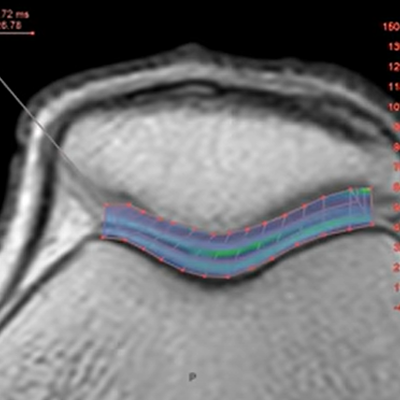

Using MR data with different TE and spin lock times, this protocol measures T2, T2*, or T1rho values of the specified ROI and shows color maps.